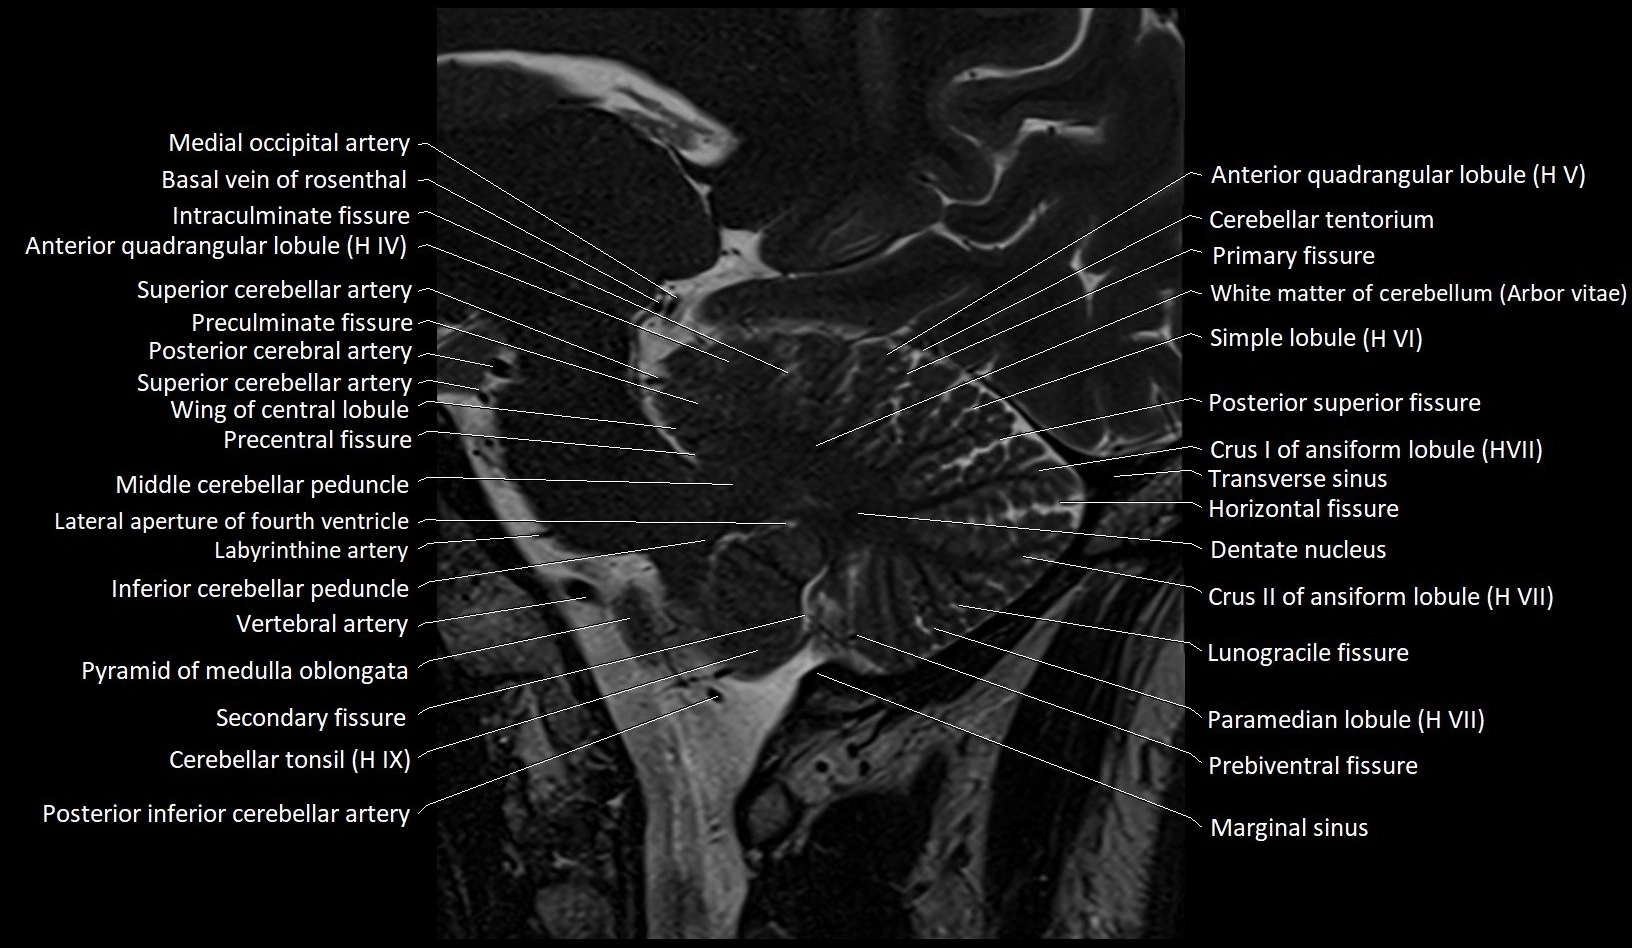

MRI images